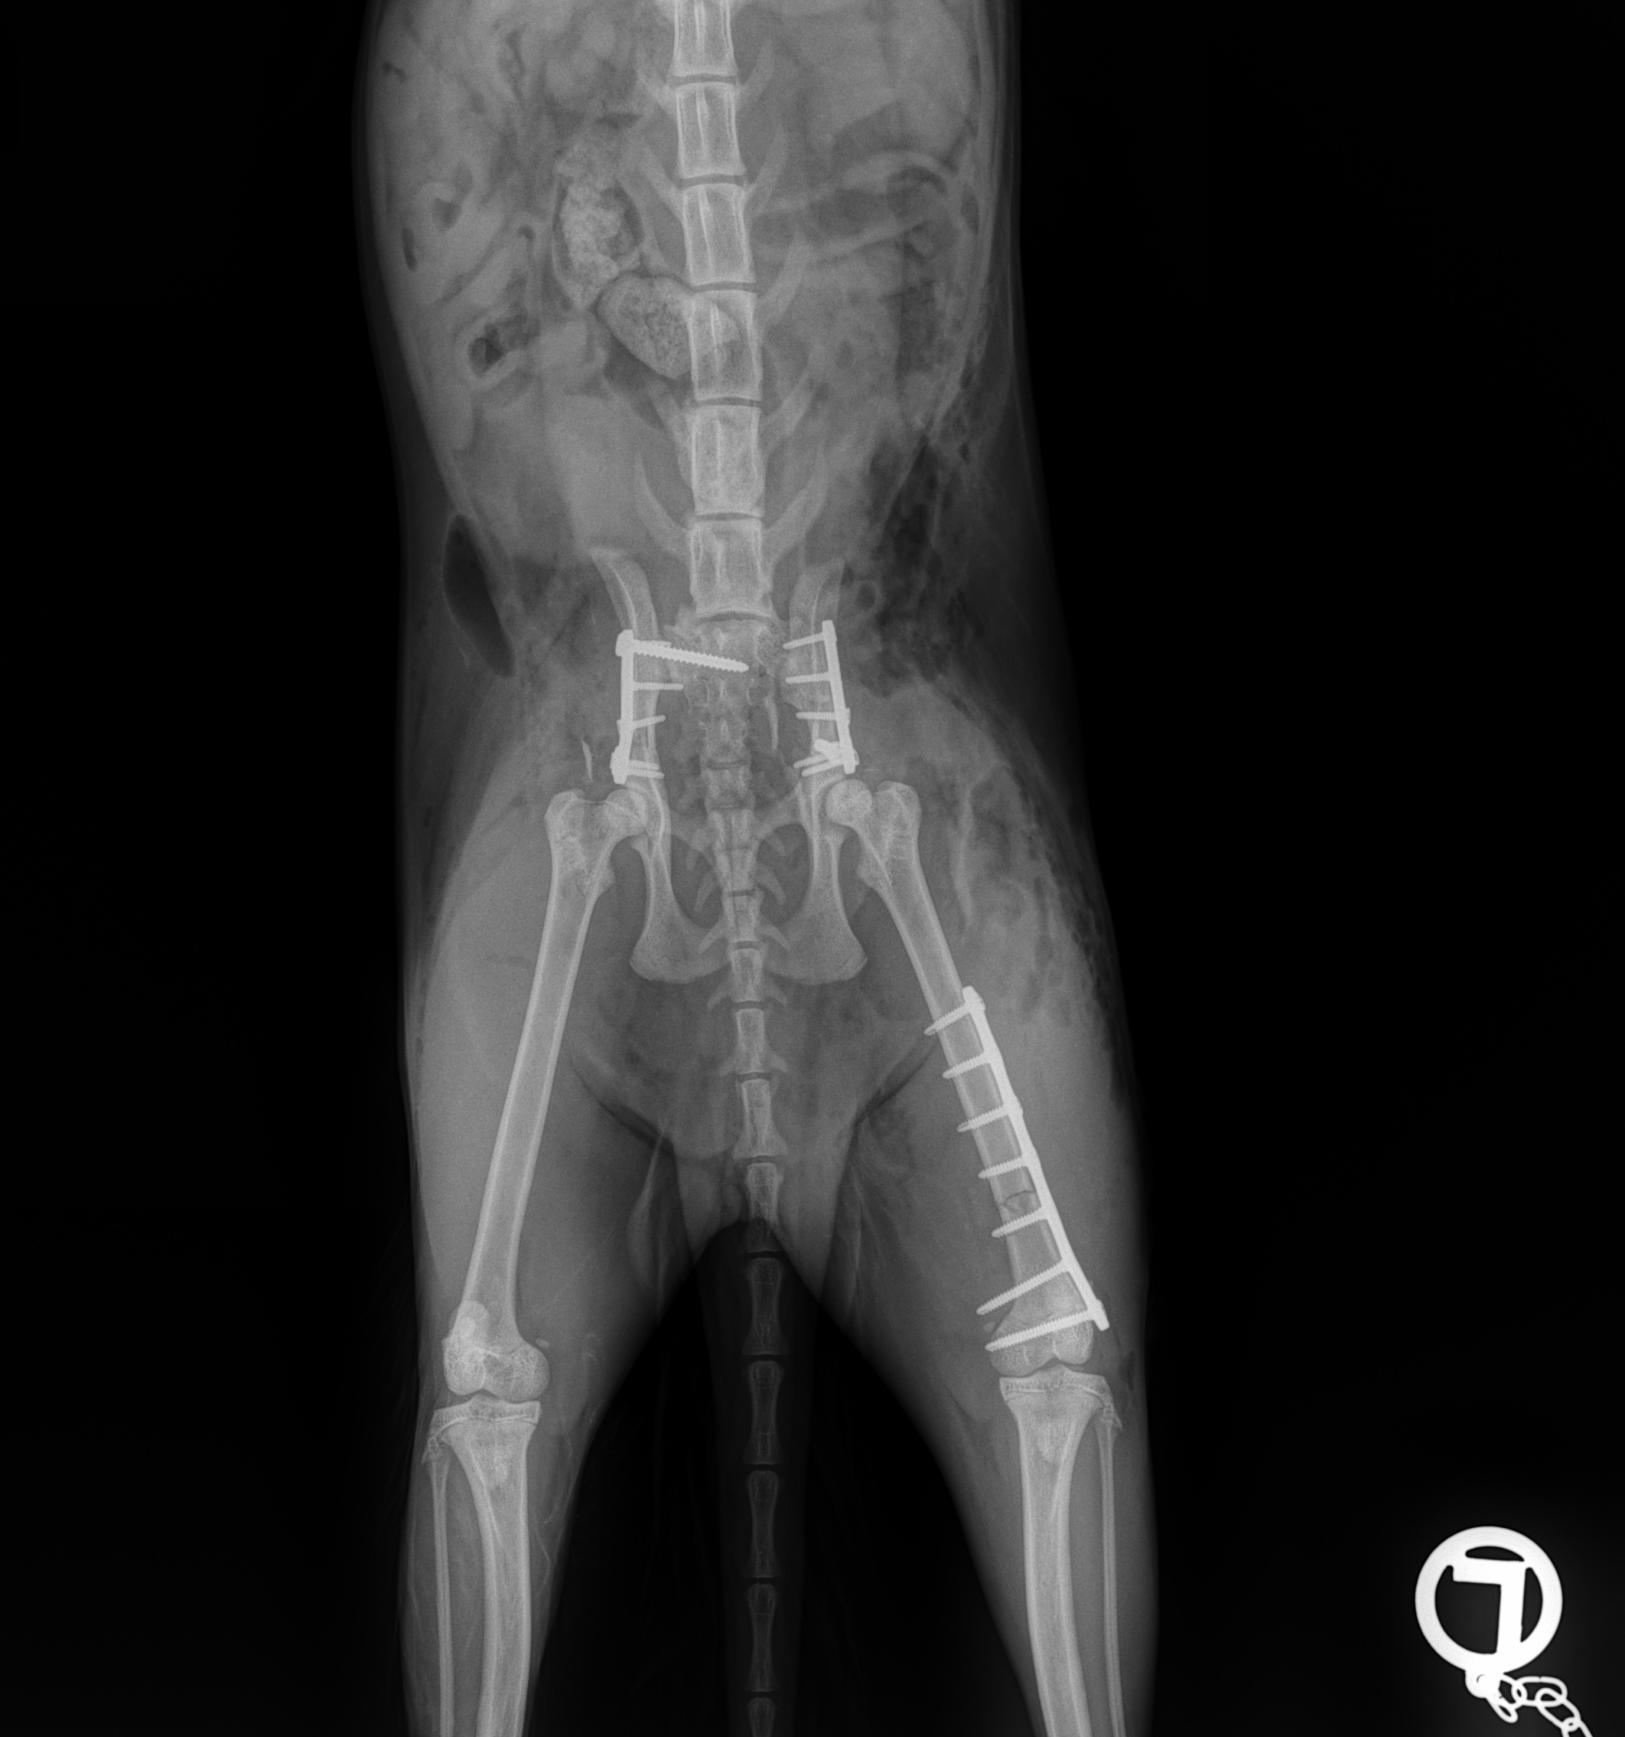

Our client Dr. Sonntag recently wrote us an email with the subject: Here’s why they changed the name of their cat to “LeiLOX”. With this email, he sent us a ton of x-rays - all of which were taken from a single cat patient.

Her owner traversed her with her car thinking it was a sack of flower soil. Sick at heart and believing her cat is going to die, but not giving up hope, the owner brought her to the animal clinic. (Spoiler alert: Dr. Sonntag bought a full LeiLOX kit 5 days before). Can you imagine what Dr. Sonntag was going to expect?

Day 1: He had to fix a humerus spiral fracture (left) with a LeiLOX bridge plate. Furthermore, he diagnosed a femur transverse fracture. Dr. Sonntag then used a 7-hole LeiLOX plate to repair this fracture, and do several emergency soft tissue surgeries.

Day 2: Repair of two iliac bone traverse fractures (left and right) with LeiLOX L-plates. Finally, several soft tissue surgeries were performed.